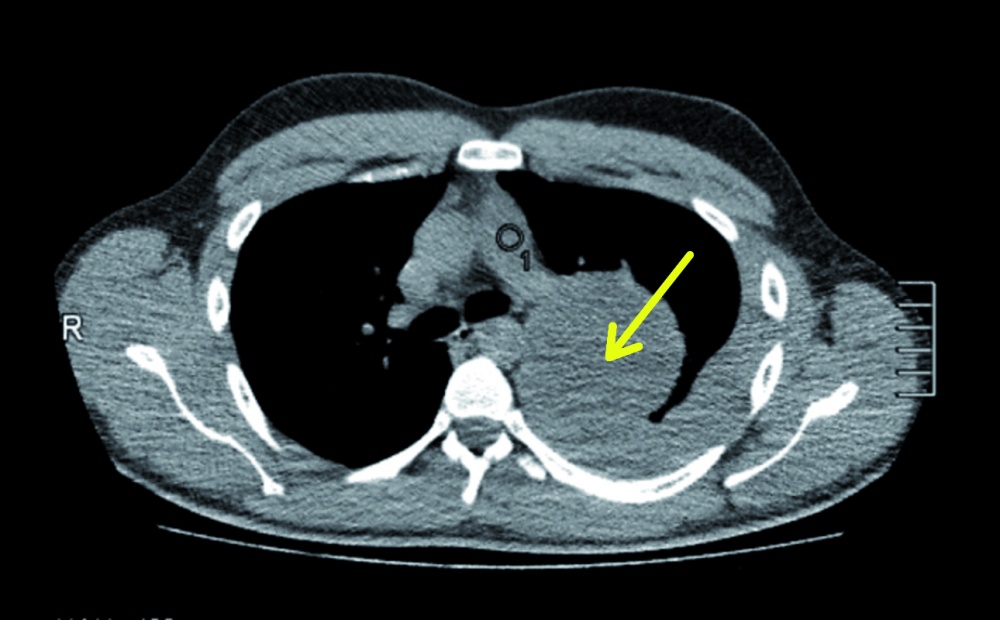

In der Nacht stellte sich ein 25-jähriger Mann in der zentralen interdisziplinären Notaufnahme des Bundeswehrkrankenhauses (BwKrhs) Ulm vor. Er war aus einer nahegelegenen Klinik aufgrund von atemabhängigen linkseitigen Thoraxschmerzen mit unklarem röntgenologischen Befund zugewiesen worden. Bei der Anamnese berichtete der Patient, dass er wenige Stunden vor der ersten Arztvorstellung beim Sport einen plötzlichen linksseitigen thorakalen Schmerz verspürt habe. Dieser sei persistent, atemabhängig und wurde von ihm mit einer Intensität von 8 (numerische visuelle Analogskala von 0 – 10) beschrieben. In einer Computertomographie des Thorax (diese wurde ohne Kontrastmittel als Trauma-CT durchgeführt, da zu diesem Zeitpunkt zunächst kein Verdacht auf das Vorliegen einer Tumorerkrankung bestand) war eine hypervaskularisierte Raumforderung von 9 x 9 x 11 cm im linken Oberlappen zu sehen. Ebenso wurde bei dieser Untersuchung der dringliche Verdacht auf einen Hämatothorax geäußert. Aufgrund einer möglicherweise erforderlichen thoraxchirurgischen Intervention mit gegebenenfalls notwendiger konsekutiver intensivmedizinischer Betreuung wurde der Patient zu uns verlegt.

Die apikale Incision wurde zur anterolateralen Thorakotomie verlängert und eine Ringfolie eingebracht, um das potenzielle -Risiko einer Tumorverschleppung zu minimieren. Wegen der lokalen Blutungsintensität und der nicht gegebenen Mobilisierbarkeit des Tumors sowie aufgrund von pleuralen Adhäsionen wurde die Indikation zur extrapleuralen Entfernung des Tumors gestellt. Hierzu erfolgte eine Incision der Pleura parietalis ungefähr 1 cm von der Anheftungsstelle des Tumors entfernt, gefolgt von einer atypischen Lungenresektion im Sinne einer Keilresektion der Segmente zwei und drei des linken Lungenoberlappens.